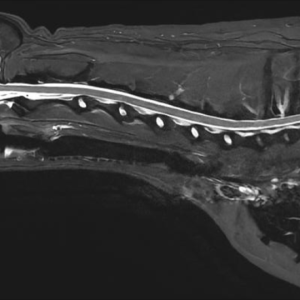

Main Gallery

Playing with a photo gallery function. It is possible to have multiple galleries, each within a namespace.